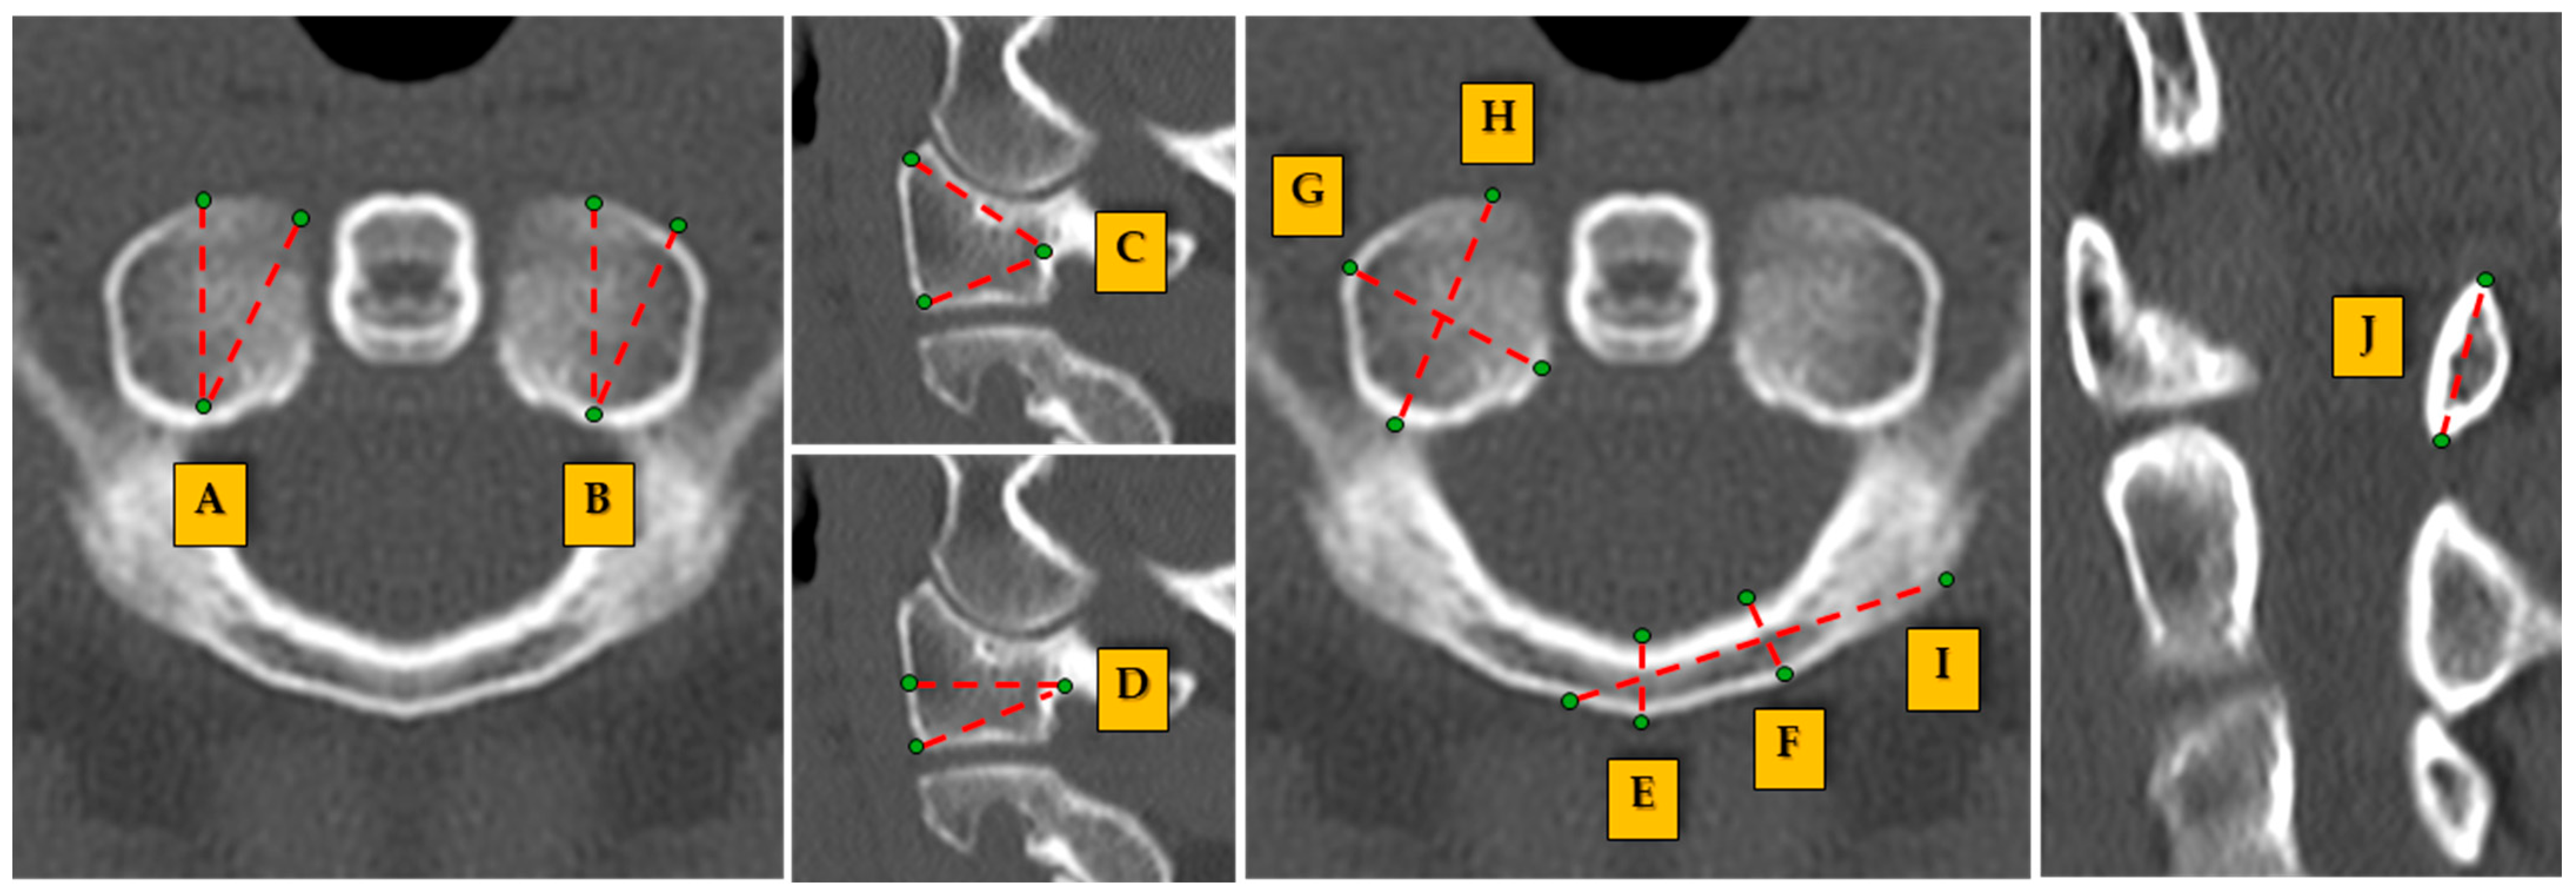

| (A) Angle of screw directed to maximal medial | 24.26 ± 2.92 | 24.50 ± 3.10 | 24.00 ± 2.70 | 0.873 | 0.062 |

| (B) Angle of screw directed to maximal lateral | 33.99 ± 7.69 | 34.20 ± 7.90 | 33.80 ± 7.50 | 0.809 | 0.852 |

| (C) Angle of screw directed to maximal cranial | 52.32 ± 4.12 | 52.10 ± 4.00 | 52.60 ± 4.20 | 0.339 | 0.170 |

| (D) Angle of screw directed to maximal caudal | 19.23 ± 1.70 | 19.50 ± 1.80 | 18.90 ± 1.60 | 0.872 | 0.845 |

| (E) Posterior tubercle bicortical diameter | 6.93 ± 1.84 | 7.00 ± 1.85 | 6.85 ± 1.82 | 0.014 | 0.011 |

| (F) Bicortical diameter | 5.63 ± 0.94 | 5.70 ± 0.95 | 5.55 ± 0.90 | 0.034 | 0.044 |

| (G) Transverse width | 12.85 ± 1.41 | 13.00 ± 1.45 | 12.70 ± 1.35 | 0.000 | 0.000 |

| (H) AP dimension | 18.57 ± 1.71 | 18.80 ± 1.75 | 18.35 ± 1.65 | 0.583 | 0.047 |

| (I) C1 lamina length | 21.79 ± 1.69 | 22.00 ± 1.75 | 21.60 ± 1.65 | 0.033 | 0.015 |

| (J) C1 lamina height | 7.78 ± 1.35 | 7.85 ± 1.40 | 7.70 ± 1.30 | 0.006 | 0.009 |